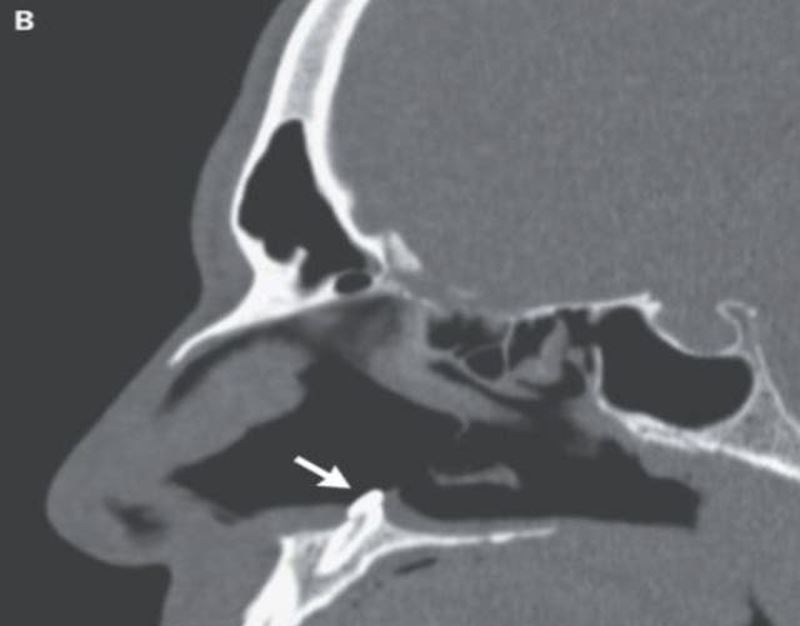

A CT scan revealed the startling diagnosis: a tooth growing inside the nasal cavity.

Medically, the man had an “inverted ectopic tooth” which developed in his nose. Ectopic teeth are when teeth grow in the wrong places which are extremely rare.